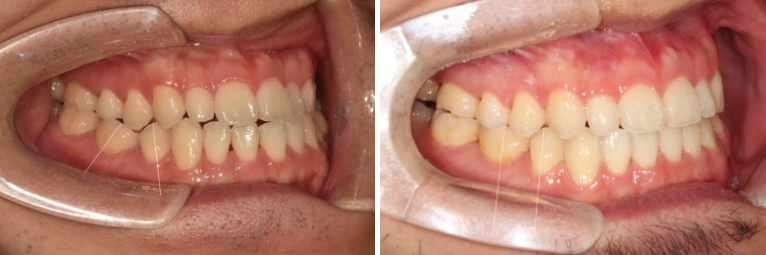

앞니 반대교합을 치료하러 오신 30대 후반의 환자분

24.01

파란화살표 작은어금니와 큰어금니가 반대교합입니다.

윗니가 아랫니를 덮지 못하는 반대교합과 절단교합이 보입니다.

어금니 교합은 3급입니다.

흰선 사이 작은어금니 하나가 결손상태이고 결손된 치아 쪽으로 주변 치아들이 쓰러져 있습니다.

파란화살표 측절치는 정상보다 작습니다.

왜소치까지는 아니지만 작습니다.